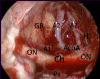

Figure 12:

Endoscopic endonasal intraoperative picture showing the suprachiasmatic area after tuberculum sellae meningioma (case in figure 11) removal. GR: gyri recta; ON: optic nerve; A1: pre-communicating tract of anterior cerebral artery; A2: post-communicating tract of anterior cerebral artery; Ch: chiasm; Ps: pituitary stalk; AcoA: Anterior communicating artery; H: heubner artery.